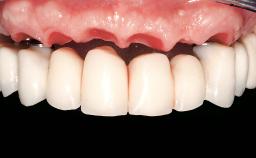

Two dental implants are placed in the same surgical session. The case concludes with the presentation of the final fixed dental prosthesis with a distal cantilever unit.